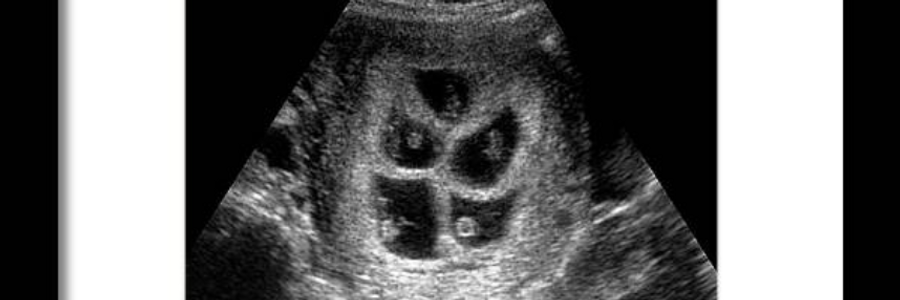

She repositions the handheld reader and gives me the faintest smile as her hand drops hard onto my abdomen. The room is deadly quiet except for the unpleasant sound of sloshing gel. Once she gets a good position, she steadies her hand. I can't tell if her hand is shaking because she's nervous or because she's older than the fossils buried under this building. The sound gradually becomes louder, and I barely hear a constant thrum of heartbeats. They sound unsynchronized and scattered, like a herd of elephants trampling the ground on a distant television.

But I hear them. The nurse moves the beacon and marks each of the five distinct heartbeats on her chart. The sound from the ultrasound intertwines with the sound from my own heart monitor machine, creating a dissonant melody. I guess that is what six hearts beating together sounds like. For a moment, I am in pure astonishment at the five lives that are developing in my womb. And then, a rippling pain seizes my abdomen. Suddenly the room is blinding white with no more shapes or dimensions and my abdomen feels like a pot of boiling acid. I feel my whole body convulsing beneath the restraints and my vision becomes dark and watery. I feel wet, and I regrettably consider that I may have peed myself due to the extreme pain. The warm wetness just makes me scream as I soil myself with no control.

Yes, there are five heartbeats in my womb right now. With mine, that made six heartbeats, like six gears turning to keep a machine running. Isn't it just a shame that my heart might give out before I can save the other five?